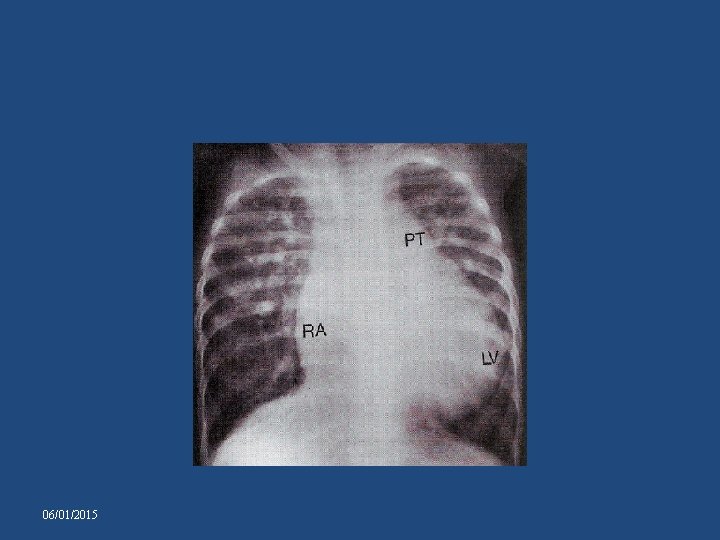

CHEST X-RAY-TA WITH NRGA AND SMALL VSD • • • Pulmonary vascularity reduced. Pulmonary artery segment – inconspicuous. Heart size – normal. Aorta prominent Right cardiac border: distinctive and prominent , accentuated by absence of RV. • LAO – Humped appearance of right cardiac border and a prominent left cardiac silhouette 06/01/2015

06/01/2015